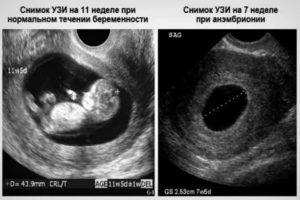

Что видно на УЗИ при замирании плода

Выделяют 2 типа замершей беременности. Каждая имеет свои отличительные особенности, отмечаемые при ультразвуковом исследовании.

Первый тип патологии характеризуется:

- диаметром яйца от 20 до 25 см с прослеживанием очевидного несоответствия размеров сроку беременности;

- отсутствием признаков зародыша внутри плодной оболочки;

- не прослушивается сердцебиение, хотя яйцо подросло;

- матка по размерам не соответствует сроку беременности;

- отсутствуют какие-либо признаки развития беременности.

При втором варианте замершей беременности диагностировать проблему сложнее, тем не менее на нее указывают:

- соответствующие сроку беременности размеры плодного яйца без зародыша внутри или с его отдельными фрагментами;

- размер плодного яйца на сроке в 10 недель достигает 50 мм;

- не наблюдается ворсинчатый хорион уже с 7-8 недели.